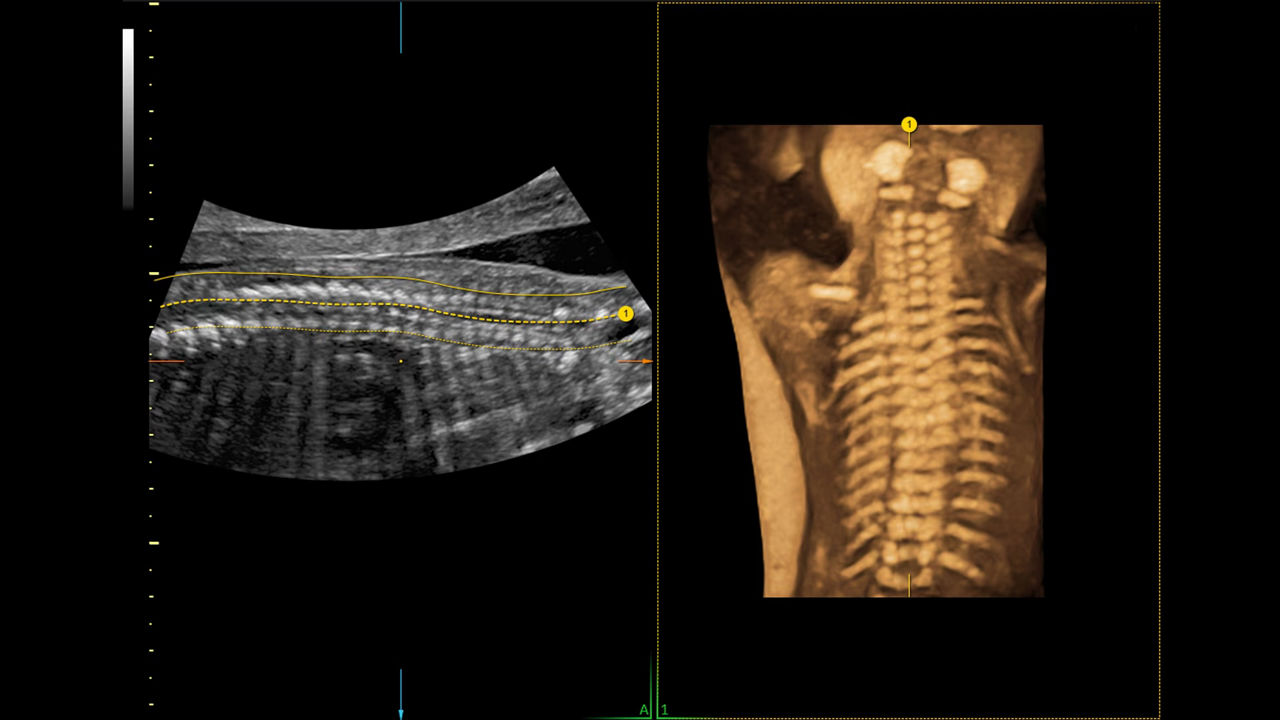

Reduce keystrokes by 83% with 3D Spine Trace